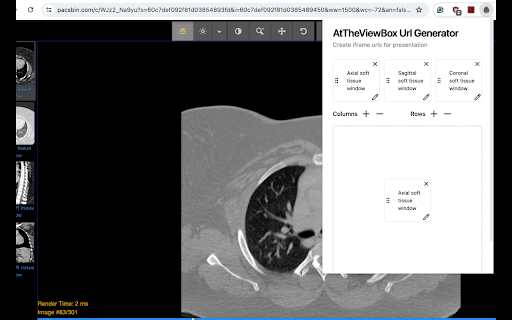

AtTheViewBox URL Generator allows users to adjust and format images from Pacsbin. A URL will be created that can be used for presentations where users can freely interact with medical images.